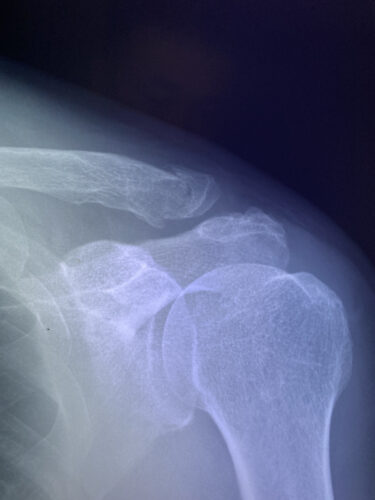

さわやか千葉県民プラザ(肩関節脱臼)

さわやか千葉県民プラザ(上腕骨外科頸骨折)

さわやか千葉県民プラザ(上腕骨外科系骨折)